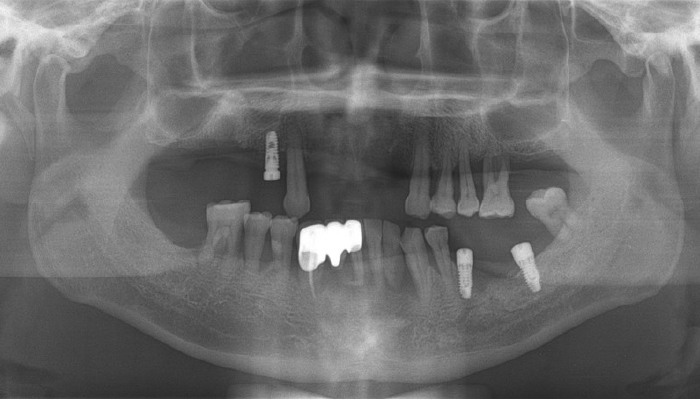

틀니 임플란트 전후 사례

• 식립전

식립후